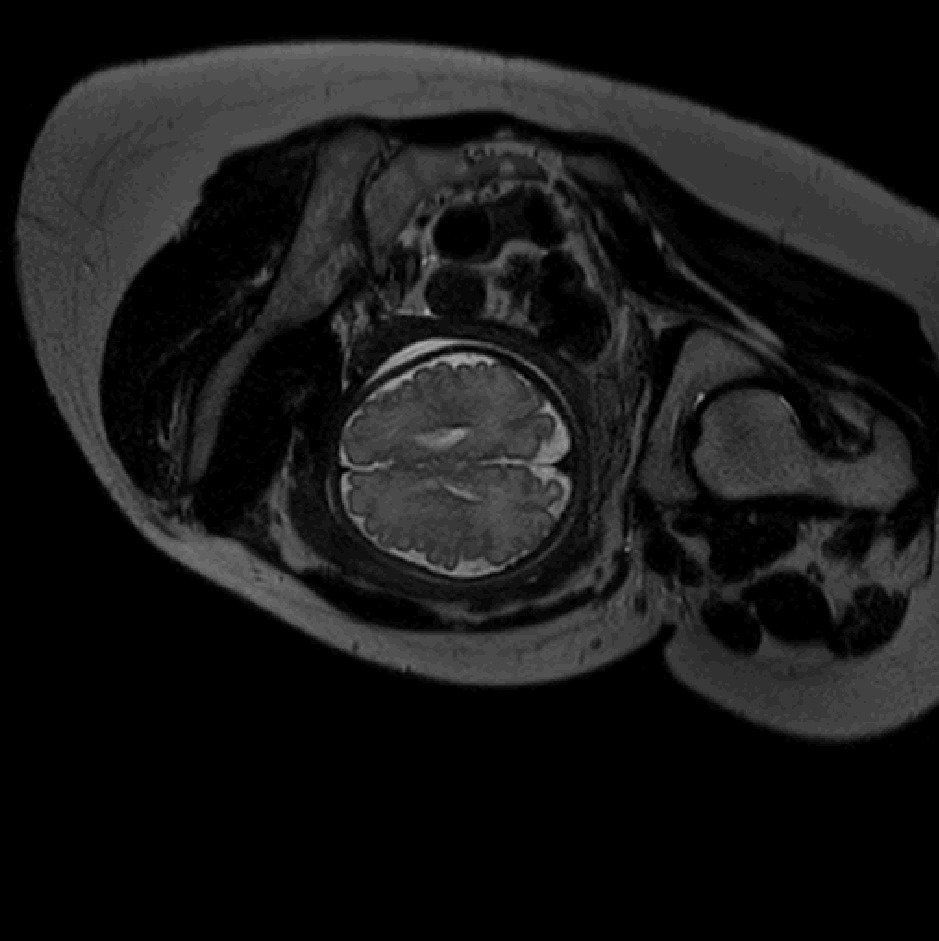

Table 1 lists average of quantitative evaluation results of these experiments and Figure 2 shows results obtained from each image. Figure 3 shows examples of the obtained segmentations.

Figure 3: Example of ICV segmentations in images acquired in axial (left), coronal (middle) and sagittal (right) planes. Top row: A slice from T2-weigted image; Second row: Automatic segmentations obtained using 7 training images from the representative imaging planes; Third row: Automatic segmentations obtained using all 21 training images from all 3 image orientations; Bottom row: Manual segmentation.